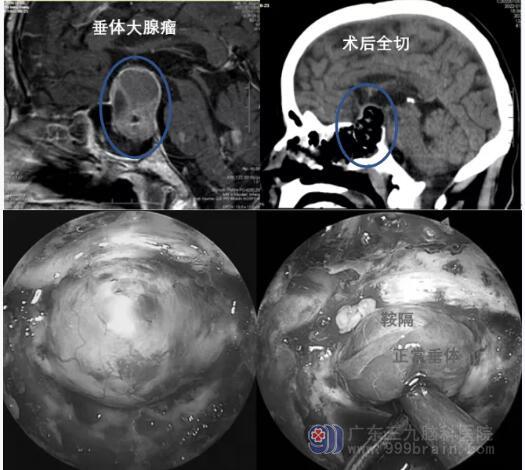

垂体腺瘤

在上世纪末和本世纪初,神经内镜经鼻微创手术已成为垂体腺瘤外科治疗的标准。神经内镜切除垂体瘤术后,脑脊液漏发生率较低、手术时间短、患者出现尿崩症和不适状况较少。对于60%~80%的大型和巨大垂体腺瘤,神经内镜下经扩大鼻蝶入路手术能达到全切或接近全切。